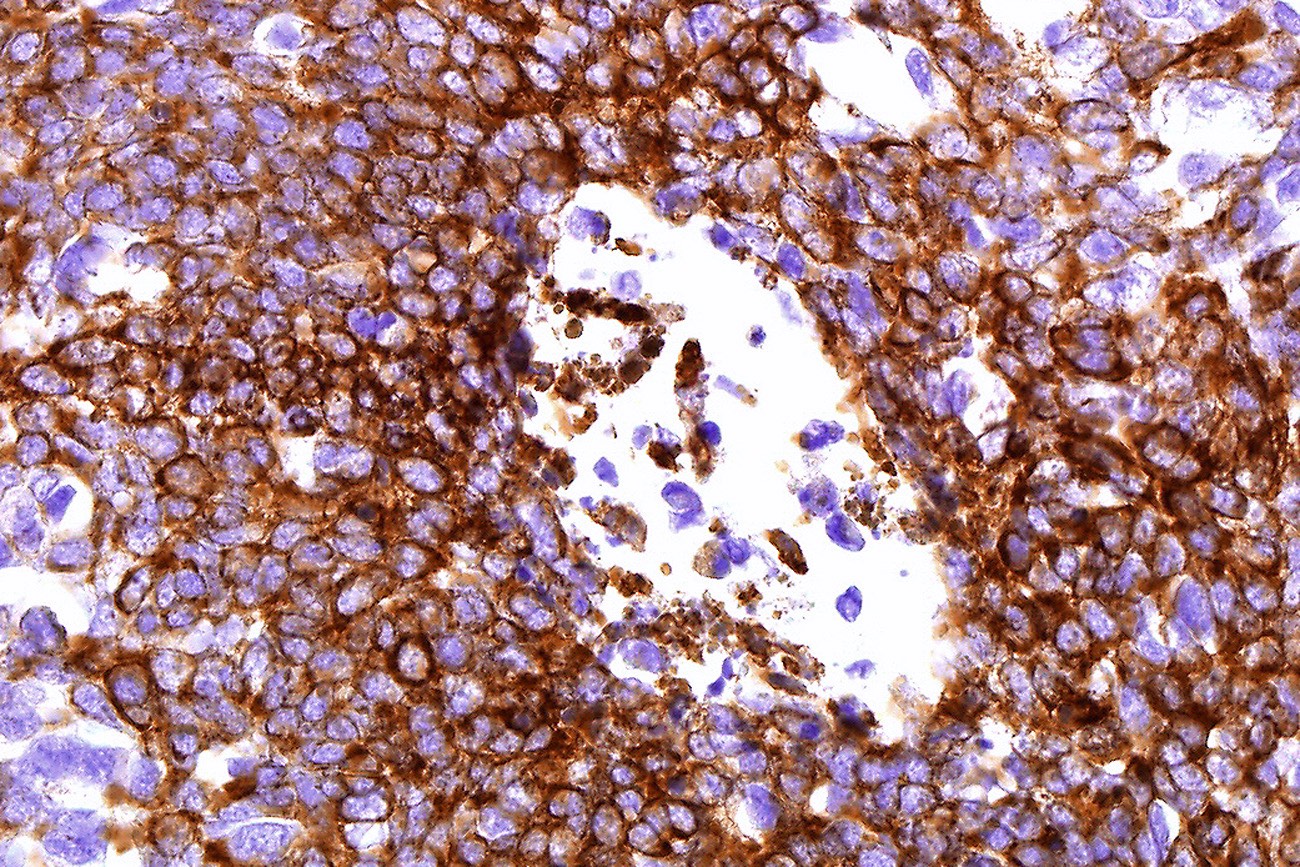

Positive stains

- CK AE1 / AE3 (100%), BerEP4 (80 - 100%), p63 (100%), CAM 5.2 (20 - 95%), androgen receptor (33 - 66%), p53 (74.5 - 83%), 34 beta E12 (high molecular weight CK), BCL2 (diffuse pattern), CD10 (positive in tumor cells, negative in stroma) (Dermatopathology (Basel) 2015;2:15, Arch Pathol Lab Med 2017;141:1490, Rom J Morphol Embryol 2018;59:1115, Am J Pathol 1992;141:25)

Microscopic (histologic) images

Contributed by Antonina Kalmykova, M.D., Phillip H. McKee, M.D., Sate Hamza, M.D., Eduardo Calonje, M.D.,

Wayne Grayson, M.B.Ch.B., Ph.D., James Sampson, M.B.B.S., M.Sc. and Assia Bassarova, M.D., Ph.D.